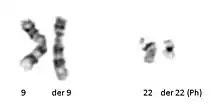

Acquired cytogenetics: In 1960, Peter Nowell and David Hungerford[21] discovered a small chromosome in the white blood cells of patients with Chronic myelogenous leukemia (CML). This abnormal chromosome was dubbed the Philadelphia chromosome - as both scientists were doing their research in Philadelphia, Pennsylvania. Thirteen years later, with the development of more advanced techniques, the abnormal chromosome was shown by Janet Rowley to be the result of a translocation of chromosomes 9 and 22. Identification of the Philadelphia chromosome by cytogenetics is diagnostic for CML. More than 780 leukemias and hundreds of solid tumors (lung, prostate, kidney, etc.) are now characterized by an acquired chromosomal abnormality, whose prognostic value is crucial. The identification of these chromosomal abnormalities has led to the discovery of a very large number of "cancer genes" (or oncogenes). The increasing knowledge of these cancer genes now allows the development of targeted therapies, which transforms the prospects of patient survival. Thus, cytogenetics has had and continues to have an essential role in the progress of cancer understanding. Large databases (Atlas of Genetics and Cytogenetics in Oncology and Haematology, COSMIC cancer database, Mitelman Database of Chromosome Aberrations and Gene Fusions in Cancer) allow researchers and clinicians to have the necessary corpus for their work in this field.

In the late 1960s, Torbjörn Caspersson developed a quinacrine fluorescent staining technique (Q-banding) which revealed unique banding patterns for each chromosome pair. This allowed chromosome pairs of otherwise equal size to be differentiated by distinct horizontal banding patterns. Banding patterns are now used to elucidate the breakpoints and constituent chromosomes involved in chromosome translocations. Deletions and inversions within an individual chromosome can also be identified and described more precisely using standardized banding nomenclature. G-banding (utilizing trypsin and Giemsa/ Wright stain) was concurrently developed in the early 1970s and allows visualization of banding patterns using a bright field microscope.

Diagrams identifying the chromosomes based on the banding patterns are known as idiograms. These maps became the basis for both prenatal and oncological fields to quickly move cytogenetics into the clinical lab where karyotyping allowed scientists to look for chromosomal alterations. Techniques were expanded to allow for culture of free amniocytes recovered from amniotic fluid, and elongation techniques for all culture types that allow for higher-resolution banding.